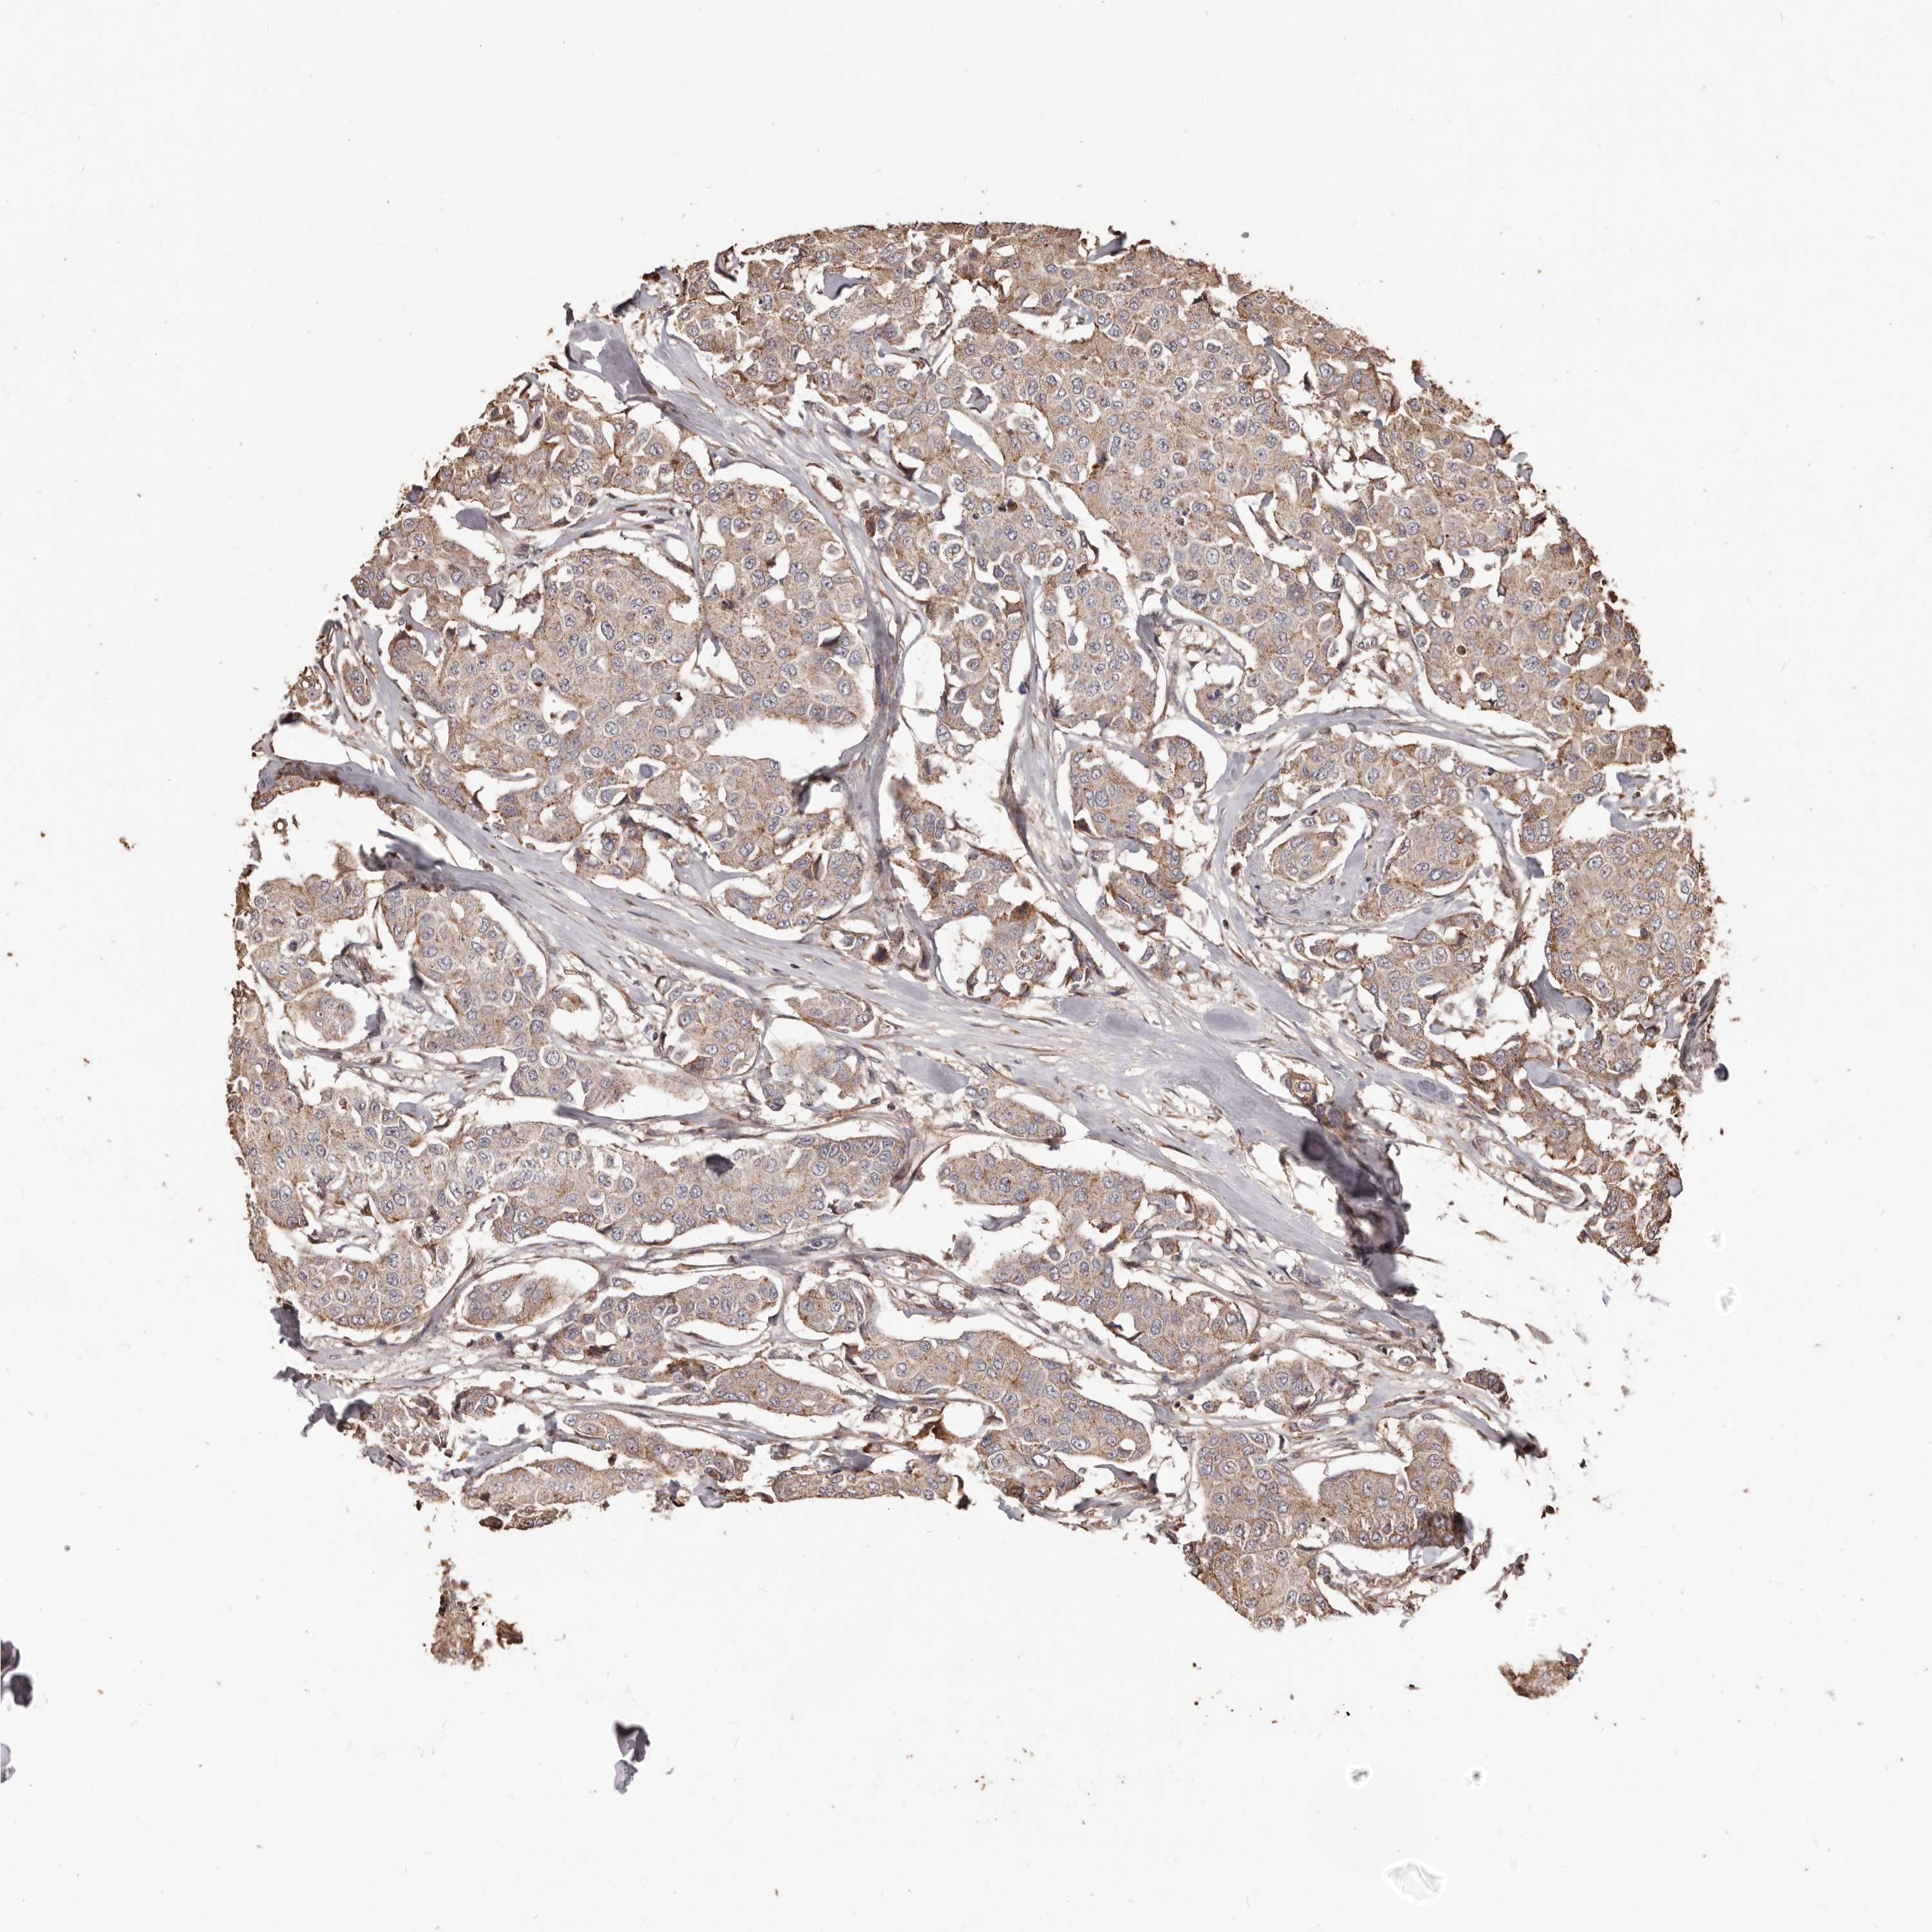

CANCER BREAST CANCER Show tissue menu

BRCA TCGA BRCA VALIDATION PROTEIN EXPRESSION

ANTIBODIES

AND

VALIDATION